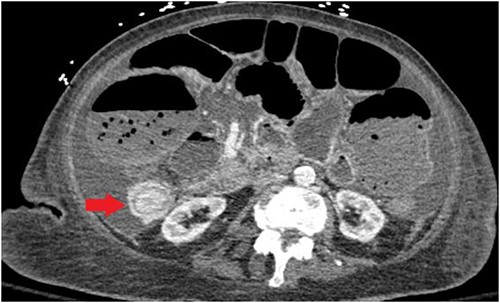

Unfortunately, the patient was diagnosed in April 2021 with complaints of nausea and vomiting and subsequently was found to have an intestine lesion causing intussusception and obstruction, which was perforated, resulting in an emergent surgical exploration and a palliative ileostomy (Fig. 3).

CT abdomen/pelvis displaying intussusception of terminal ileum.